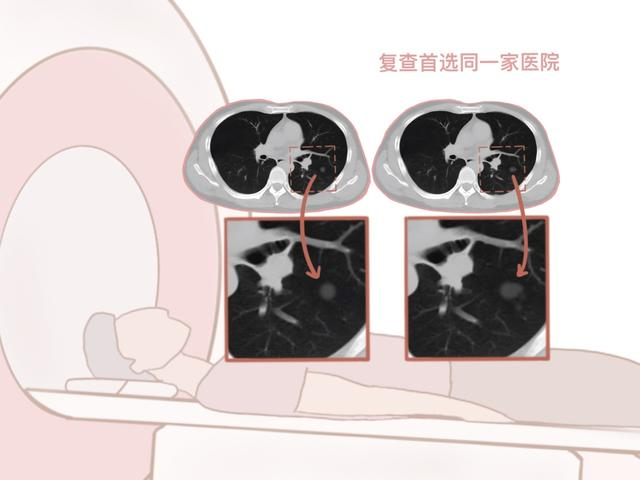

误区:换一家医院随访复查

错!复查首选同一家医院。医生可以在电脑上把结节局部放大,对比直径、密度、实性成分等,有利于肺磨玻璃结节的精准判定。不同医院打印的胶片很难对比读片。